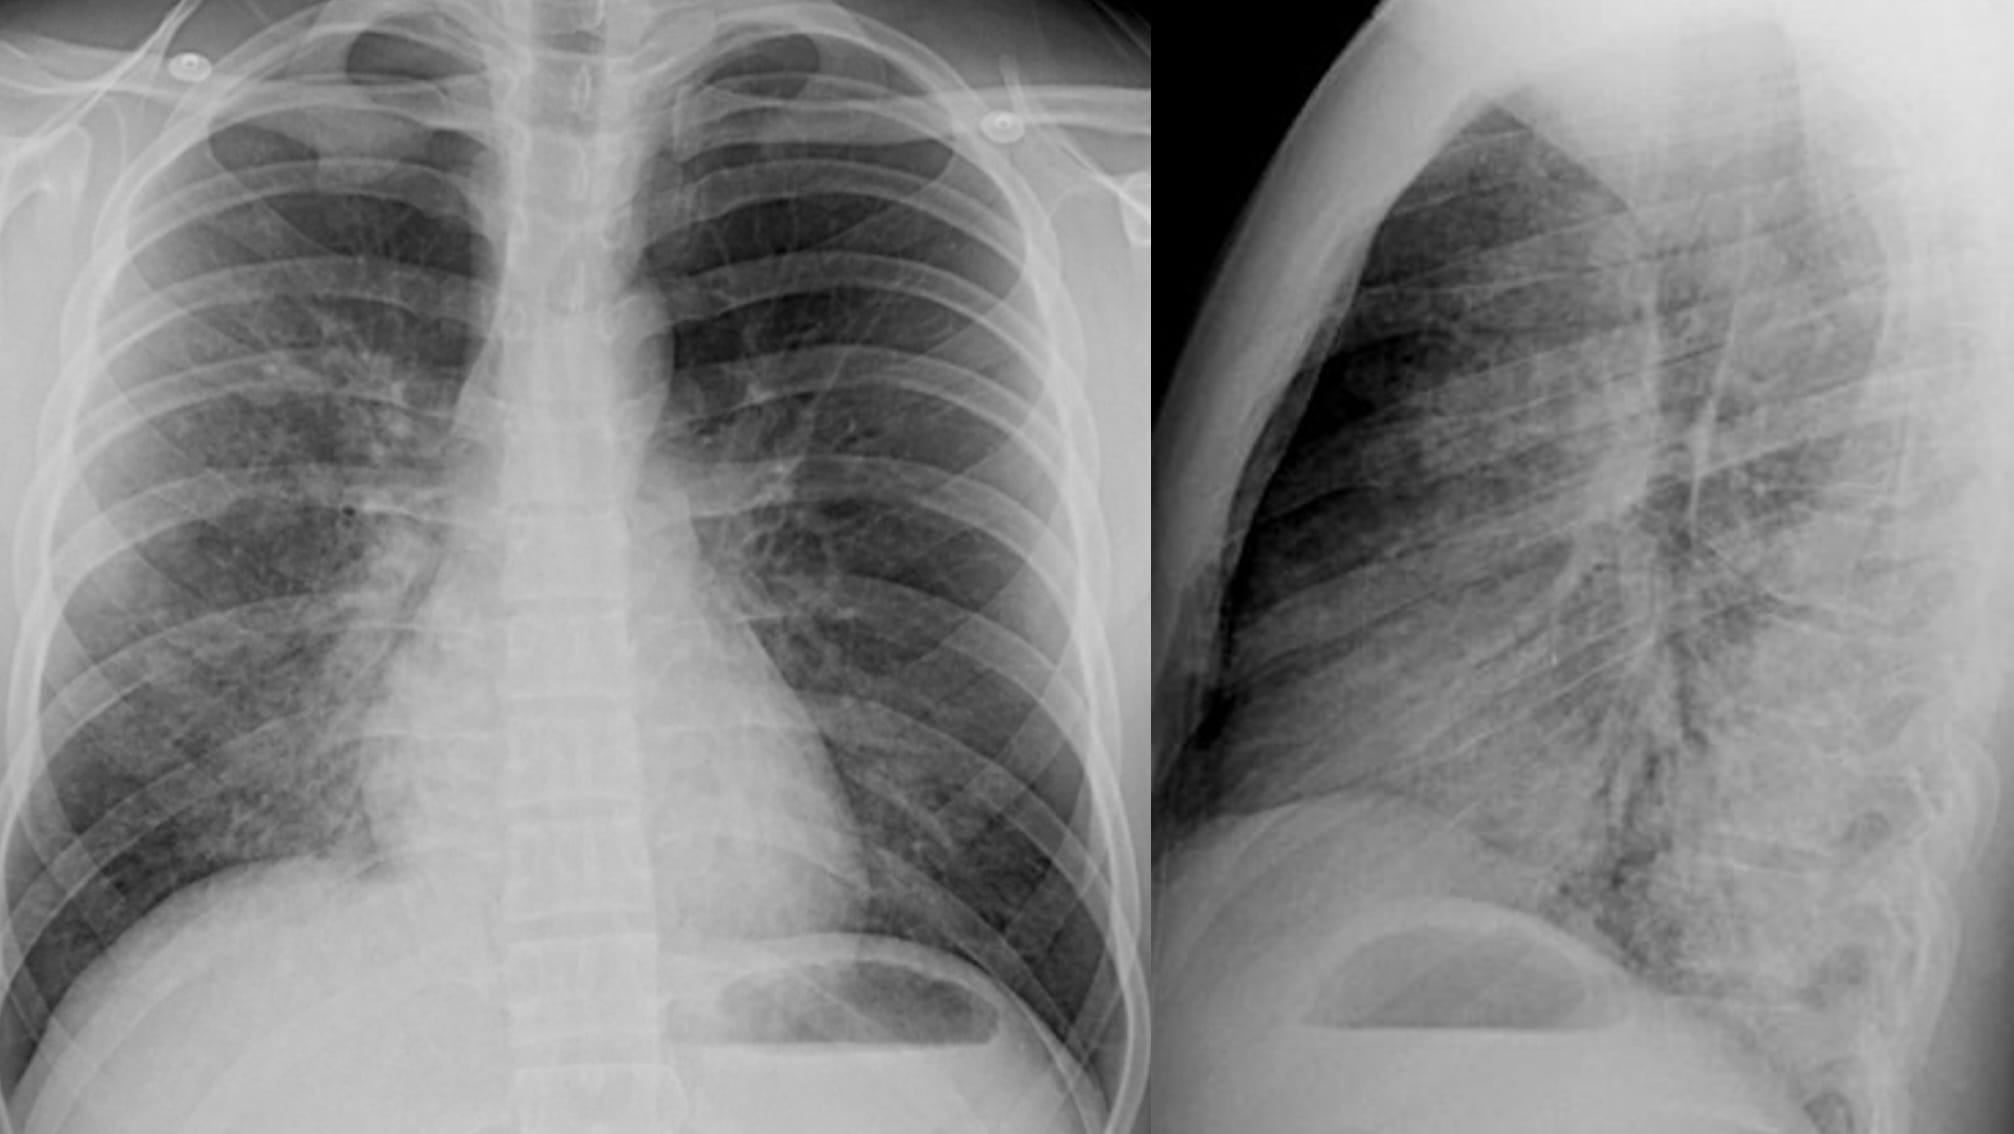

Unexplained, new dyspnea in a healthy female

- lymphatic obstruction, typically by metastatic tumor–lymphangitic tumor spread–manifests as lung edema

- the edema is typically interstitial, may be focal and asymmetric, and associated with transudative pleural effusions

- lymphangitic tumor spread may be accompanied by other forms of metastases, such as solid nodules

- uncommonly, lymphangitic tumor spread is the first manifestation of cancer